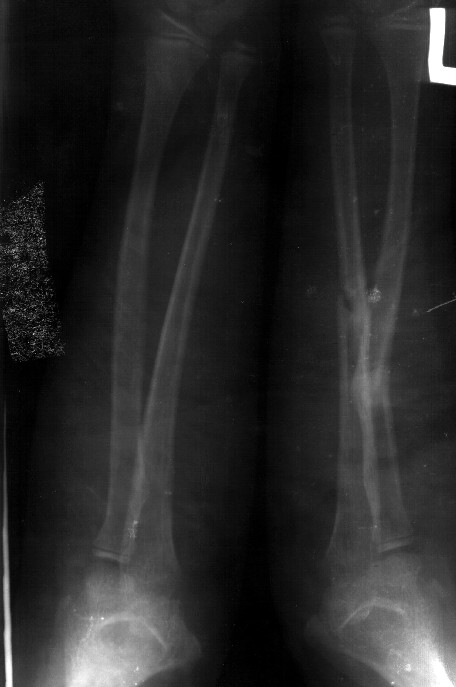

Сделал симметричные снимки с максимальной супинацией и пронацией при согнутом предплечье в 90 град. Объем ротационных движений 90-100 град.

С ув. Сергей Мелашенко

Снимок один сделан с супинацией, второй - оба предплечья в одинаково нейтральном положении. то есть по этим снимкам объем ротационных движений не оценить. Снимко в двух проекциях лучше и делать в среднем положении между пронацией и супинацией, то есть обе проекции в однм и том же положении, когда линия, проходящая через шиловидные отростки, идет в плоскости головки. Прошу прощения за усложнение простых вещей.